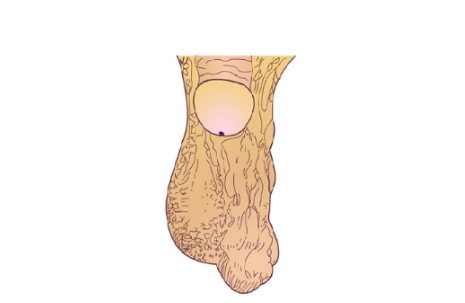

精索靜脈曲張圖片

精索曲張睪丸下墜時